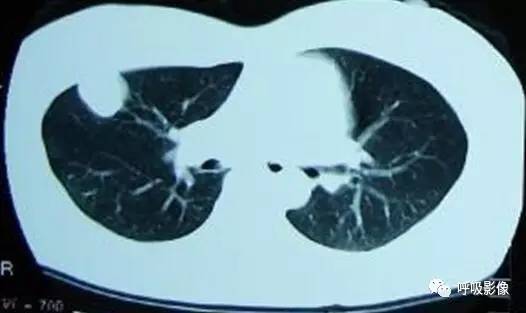

简单病史:女,35岁。查体发现肺部占位。胸部CT;右肺中叶外侧段近胸壁处圆形病变,边缘光滑,无毛刺, 增强扫描可见强化。

诊断: 肺良性肿瘤或孤立性转移瘤

诊断依据:青年女性,右肺中叶结节影,边缘光滑,密度均匀,无明显分叶、毛刺,临近胸膜无受累、肋骨无压迹,不符合肺恶性肿瘤诊断;患者无症状,不符合感染性疾病;病变密度均匀,内无坏死,无卫星灶,不符合结核球诊断。综合考虑肺良性肿瘤或孤立性转移瘤可能性大,病变位于胸膜下,孤立性转移瘤需考虑。病变增强扫描可见血管样强化,提示原发瘤血供丰富,最终病理为绒毛膜癌肺转移。